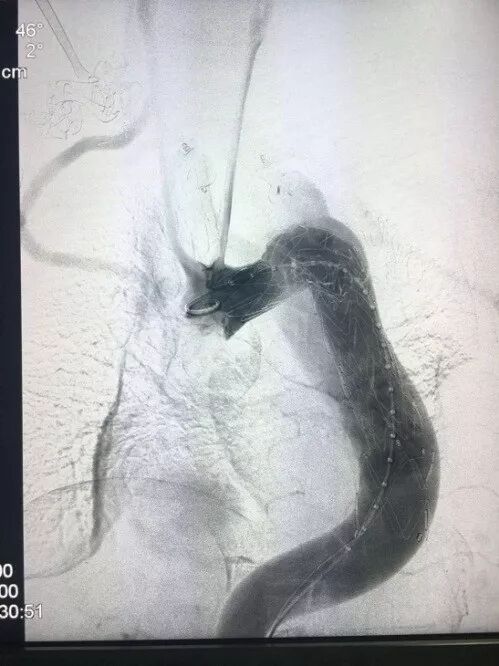

病例1:主动脉瘤,术前造影显示(图1),II型弓,迷走右锁骨下动脉,动脉瘤累及左锁骨下动脉,降主动脉迂曲严重;

图1  术前造影-病例1